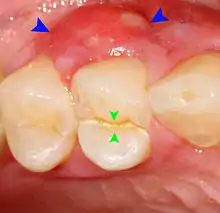

Food impaction

Food impaction occurs when food debris, especially fibrous food such as meat, becomes trapped between two teeth and is pushed into the gums during chewing.[6]:125–135 The usual cause of food impaction is disruption of the normal interproximal contour or drifting of teeth so that a gap is created (an open contact). Decay can lead to collapse of part of the tooth, or a dental restoration may not accurately reproduce the contact point. Irritation, localized discomfort or mild pain and a feeling of pressure from between the two teeth results. The gingival papilla is swollen, tender and bleeds when touched. The pain occurs during and after eating, and may slowly disappear before being evoked again at the next meal,[nb 1] or relieved immediately by using a tooth pick or dental floss in the involved area.[6]:125–135 A gingival or periodontal abscess may develop from this situation.[21]:444–445